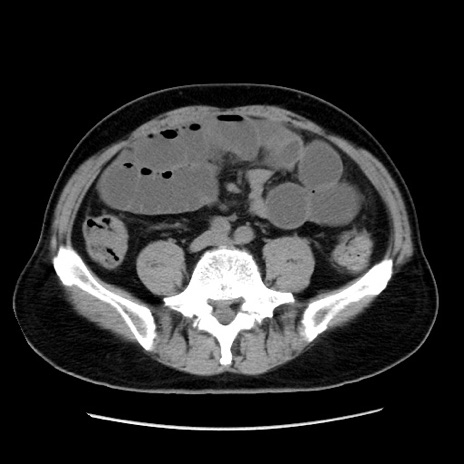

症例16(横断像)

【症例】 70歳代男性

【主訴】 腹痛、嘔吐

【現病歴】 約1ヶ月前より間欠的に腹痛と嘔吐あり、当院消化器内科を受診したところCTで多発する肝臓のLDAを指摘され、精査中であった。以降は消化器症状は安定していたが、2日前より嘔気と腹痛があり、同日より排便・排ガスが消失した。改善認めず、 本日、救急外来を受診した。

【既往歴】 大腸ポリープ切除後。

【身体所見】意識清明・会話良好、BT 36.3℃、BP 127/80mmHg、 P 80bpm、腹部:膨満あり、平坦・軟、上腹部正中および下腹部正中に圧痛あり、反跳痛なし、筋性防御なし。

【データ】WBC 7200、CRP 0.77